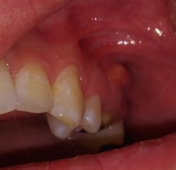

Подскажите, пожалуйста. Болела десна около недели, незначительно. Позже образовался какой-то шарик, похожий на прыщик. А после, во время еды что-то стало мешать и вот появилось непонятное новообразование из десны. На ощупь твердое, беспокоит во время приема пищи.

Очень сложно определить, но все Ваши симптомы говорят и свищевом выходе. То есть, на верхушках зуба имеется воспалительный процесс.